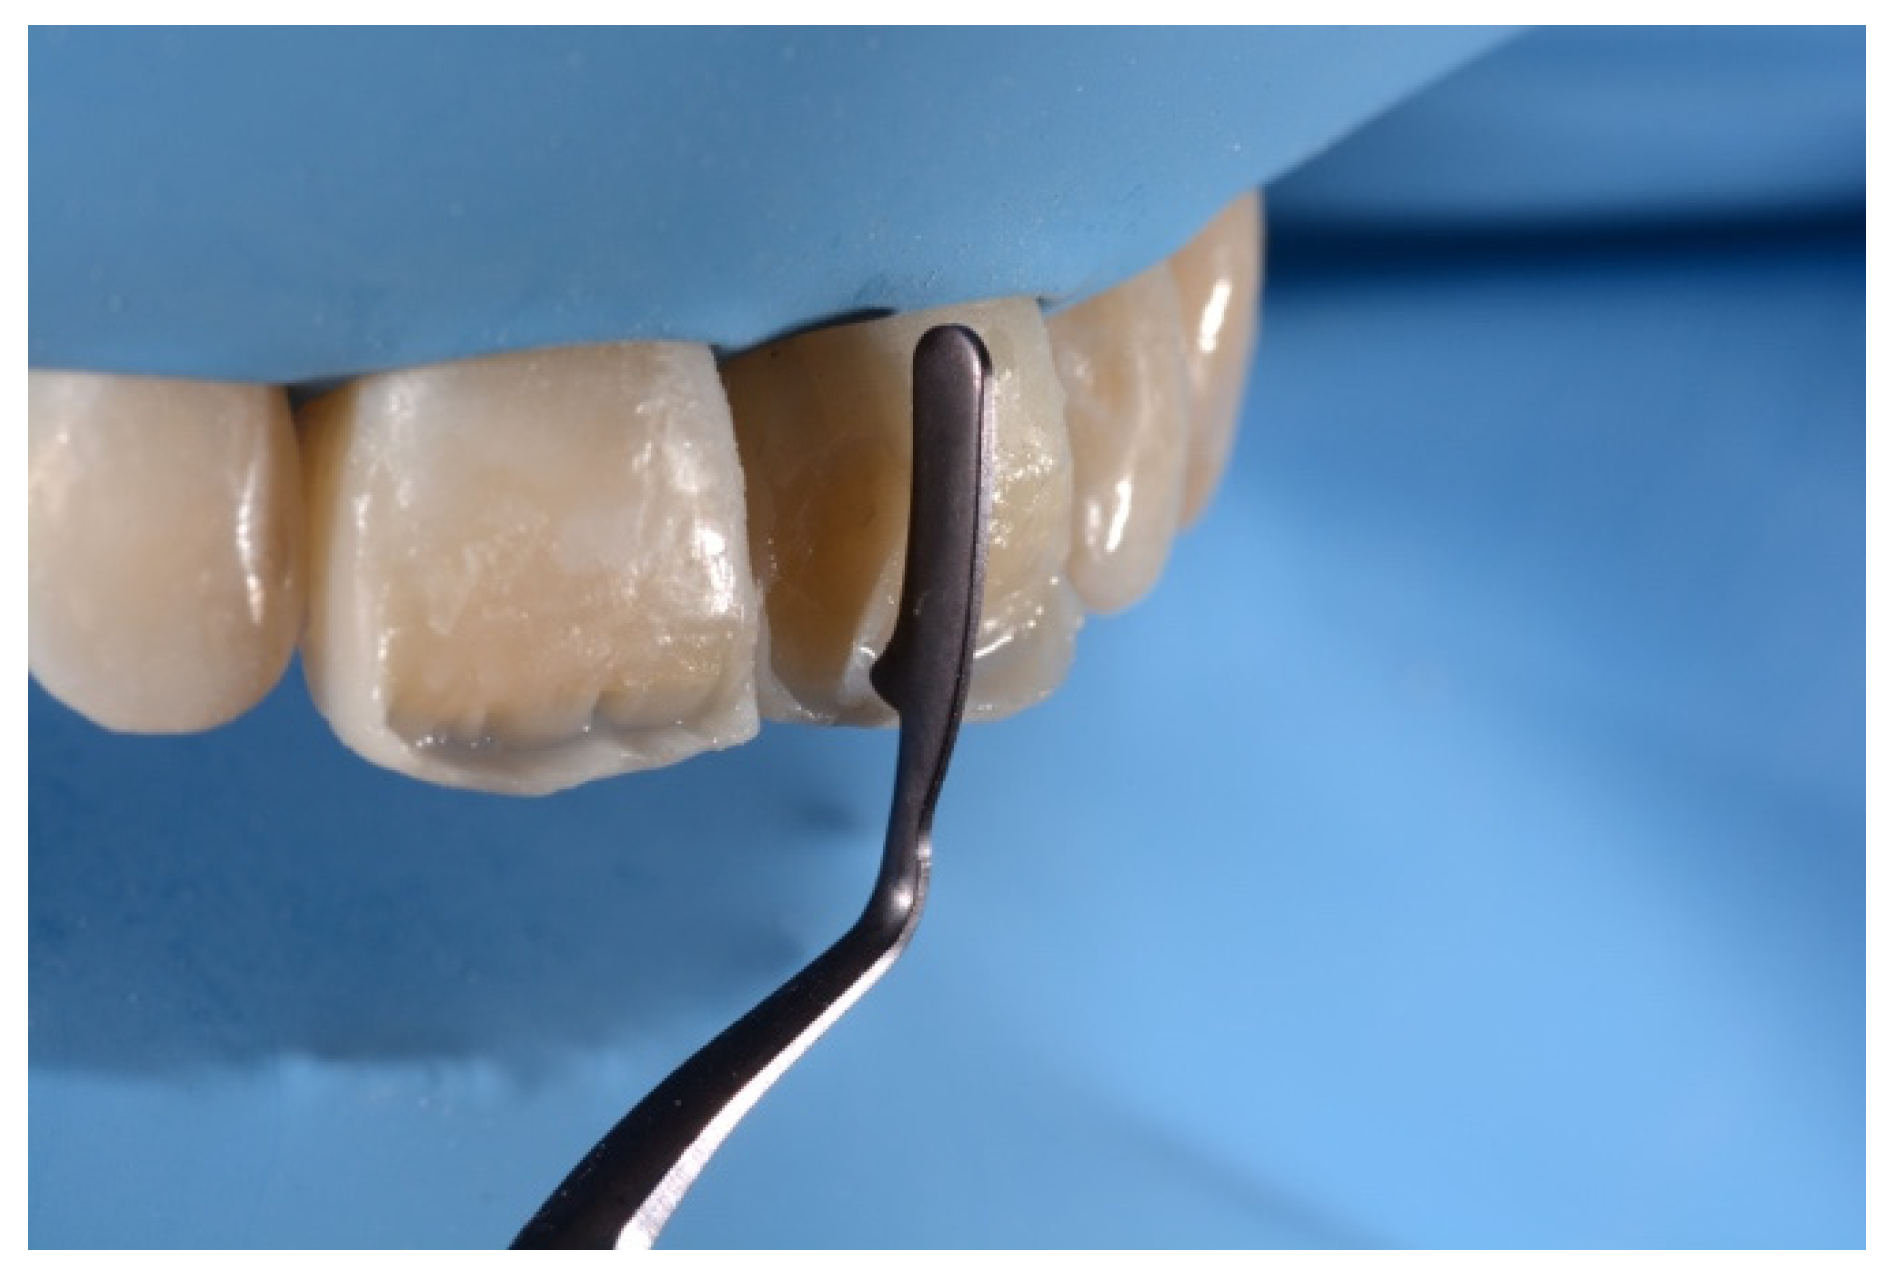

- Building interproximal walls with matrices;